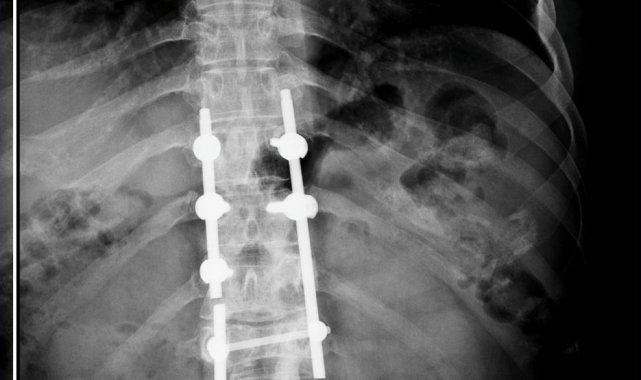

Konya'daki Afşar ve Bağbaşı Barajı arasındaki Mavi Tünel'in inşaatında Palet İnşaat bünyesinde ekskavatör operatörü olarak çalışan Sezgin Keşto (31), 1 Mart 2019'da, Cezmi Çelik'in (54) kullandığı beton mikserinin kaza yapması sonucu ağır yaralandı. Bu sırada sürücü Cezmi Çelik ise hayatını kaybetti. Araçtan çıkarıldıktan sonra Selçuk Üniversitesi Tıp Fakültesi Hastanesi'ne kaldırılan Keşto'nın omurgasının kırıldığı, omuriliğinin zedelendiği belirlendi. Geçirdiği ameliyatın ardından 3 gün yoğun bakımda kalan Keşto, 6 aylık tedaviden sonra taburcu edildi. Bir daha yürüyemeyeceğini öğrenen Keşto, Adana'daki ailesinin evine döndü.